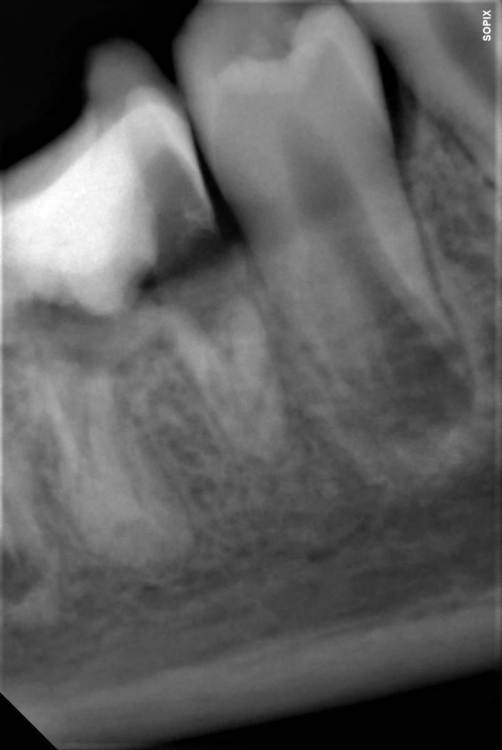

koreandr Опубликовано 7 декабря, 2022 Поделиться Опубликовано 7 декабря, 2022 (изменено) Привет, ребята! С детьми не работаю совсем. Подскажите, пожалуйста, какие тренды сейчас в таком случае. Удалять/ждать. Если ждать то чего? Ребенок 11 лет, зуб 46, возможно резорцин. Я думал это удалять, родители в сомнениях. Изменено 7 декабря, 2022 пользователем koreandr Ссылка на комментарий

DoctorT Опубликовано 7 декабря, 2022 Поделиться Опубликовано 7 декабря, 2022 (изменено) Здесь 45 спасать нужно, тк тень уже на апроксималке. ((( Я не детский врач, но может 46, пломбировка дастального канала, гемисекция + врем. протезирование до формирования постоянного прикуса, а затем уже имплантация. Изменено 7 декабря, 2022 пользователем DoctorT 1 Ссылка на комментарий

IvanK Опубликовано 9 декабря, 2022 Поделиться Опубликовано 9 декабря, 2022 Здравствуйте 6 удалять, 5 - определиться по ситуации, ортодонта подключить, можно подумать о трансплантации План можно составить только после диагностики 1 Ссылка на комментарий

red_butler Опубликовано 9 декабря, 2022 Поделиться Опубликовано 9 декабря, 2022 седьмой еще посмотрите, что то там с медиальным корнем 2 Ссылка на комментарий